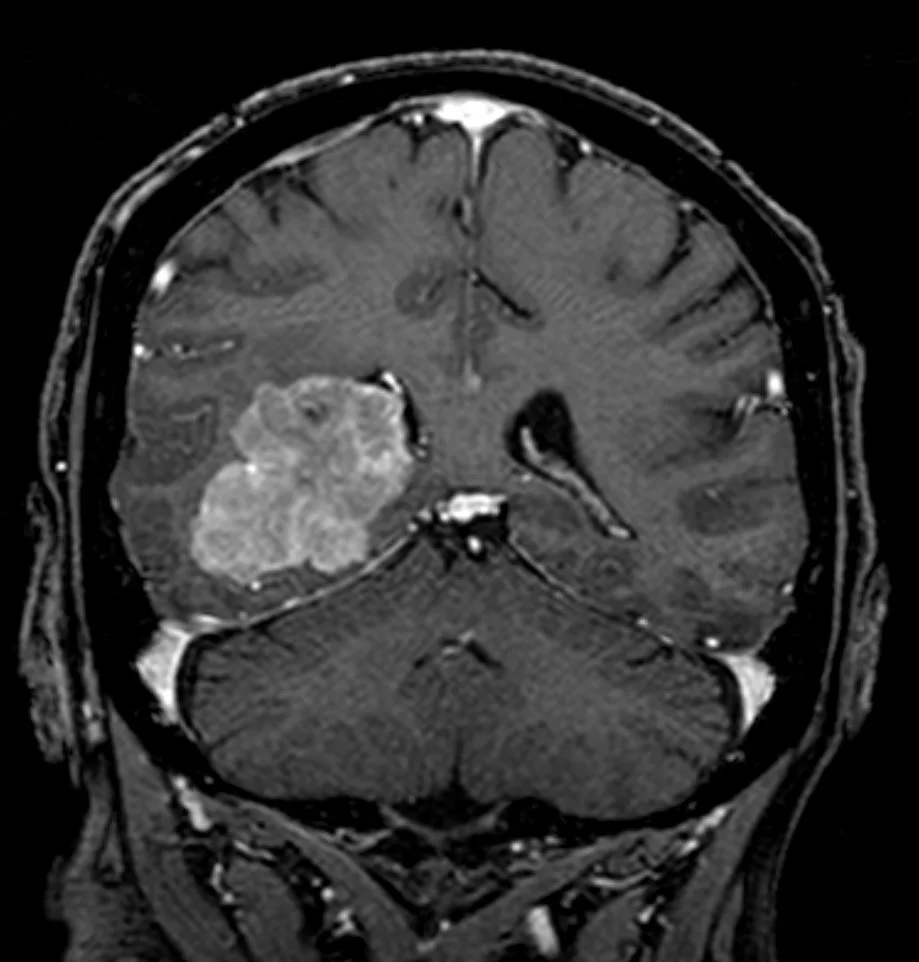

Η μαγνητική τομογραφία ανέδειξε ευμεγέθη χωροκατακτητική εξεργασία εντός της δεξιάς πλάγιας κοιλίας του εγκεφάλου.

Εδώ είναι η θέση του μηνιγγιωματος που αποτελεί τη χειρουργική πρόκληση. Πρέπει κανείς να φθάσει στον όγκο προκαλώντας την ελάχιστη βλάβη στον υπερκείμενο υγιή εγκέφαλο.

Σε περιστατικά σαν και αυτό, η καλή γνώση ανατομίας σε συνδυασμό με το νευροπλοηγό και τον διεγχειρητικό υπέρηχο βοηθούν στην επιλογή της ιδανικής οδού προσπέλασης η οποία με τη σειρά της θα μας δώσει ένα καλό κλινικό αποτέλεσμα μετεγχειρητικά.